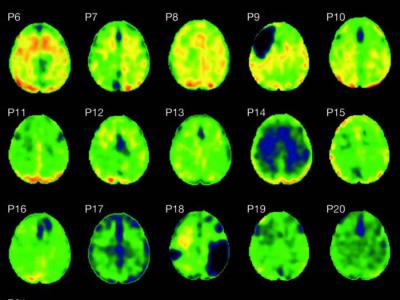

单次创伤性大脑损伤会对认知产生长期后果(Credit: N. Gorgoraptis et al., Science...